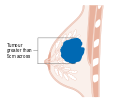

- المرحلة: مراحل سرطان الثدي باستخدام نظام TNM يعتمد على حجم tumor (T) "الورم" سواء أكان أم لم يكن منتشراً إلى العقد nodes (N) اللمفاوية تحت الإبط، أو كان الورم metastasized (M) "منتشراً" (أي منتشر لأكثر من مكان في الجسم). حجم أكبر، انتشار عقدي، والورم الخبيث له رقم مرحلة أكبر ومآل أسوأ.

- المرحلة 1–3: تكون داخل الثدي أو الغدد الليمفاوية الإقليمية.

- المرحلة 4: هو السرطان "النقيلي" الذي له مآل أقل مواتاة لانتشاره خارج الثدي والغدد الليمفاوية الإقليمية.